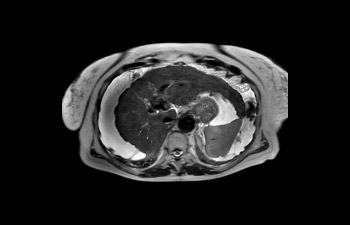

Hígado

Hígado con ascitis